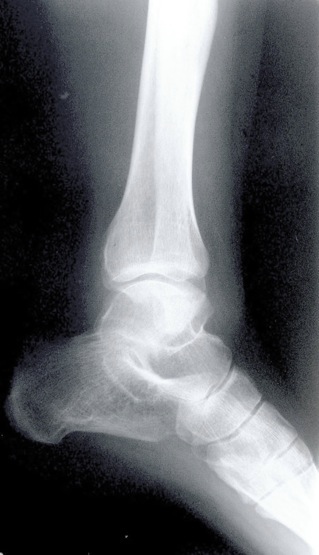

Analyse de radiographies

Radiologie

Analyse différentes radiographies. Essaye de reconnaître:

les différentes parties représentées: os, articulations,...

les malformations, les déplacements, les fractures.

l’âge des sujets: zones de croissances.